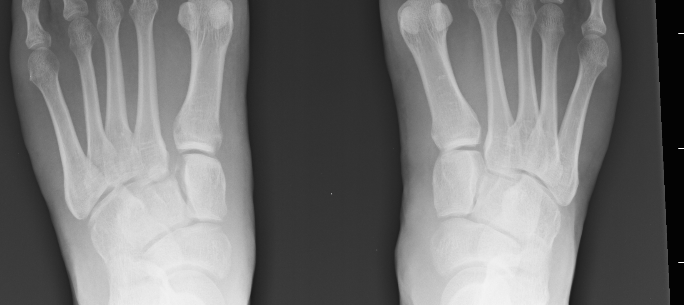

Lisfranc injuries